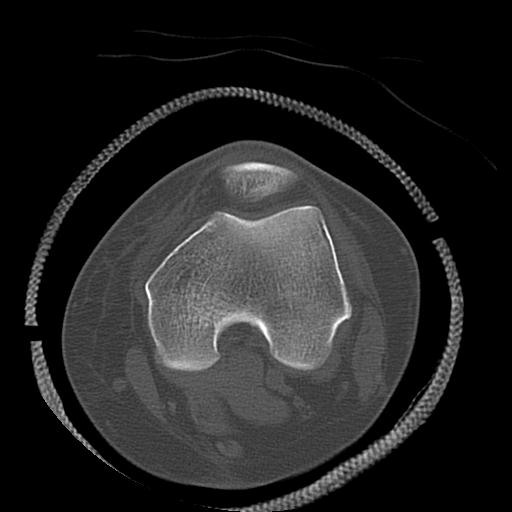

49554 3/13 膝 4R 3/16 4R 1/18 2R 78歳男性 膝蓋骨骨折